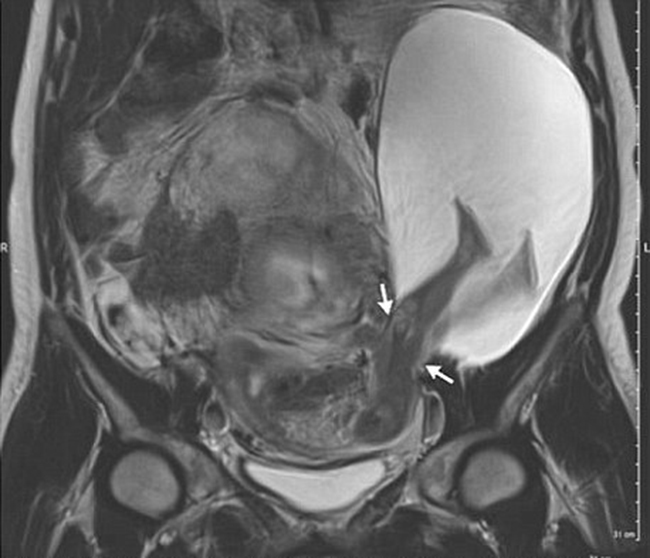

Một sản phụ 33 tuổi đã đến khám tại bệnh viện Đại học Angers và khiến các bác sĩ phải ngạc nhiên với ảnh chụp thai nhi. Theo đó, em bé trong bụng mẹ đã đạp rách cả dạ con chỉ để duỗi chân cho thoải mái. Đây có lẽ là em bé nghịch nhất thế giới.

Khi đủ thời gian thai kỳ, các em bé sẽ bắt đầu một cuộc sống mới bên ngoài bụng mẹ. Trong khi, phần lớn các bé phải nhờ tới sự trợ giúp của các bác sĩ mới có thể chui khỏi ra bụng mẹ thì một em bé sống tại Pháp đã tự mình đạp rách tử cung của mẹ để thò chân ra ngoài.

Trường hợp mang thai kỳ lạ này đã được bác sĩ Pierre Emmanuel Bouet, thuộc Bệnh viện Đại học Angers phát hiện ra sau khi nhìn thấy hình siêu âm của một sản phụ 33 tuổi. Theo bác sĩ, đây là 1 trong 26 ca mang thai cực hiếm hoi trong lịch sử y học thế giới.

Vết rách có chiều dài 2,5cm. Một phần túi nước ối cũng theo đó mà lòi ra ngoài. Trước tình trạng này, bác sĩ đã cảnh báo khả năng sinh non cũng như thoát vị tử cung, nhau cài răng lược, thậm chí phải cắt bỏ tử cung ở mẹ.

Cuối cùng, bà mẹ dũng cảm này cũng trải qua 30 tuần mang thai đầy nguy hiểm để hạ sinh một bé trai khỏe mạnh nặng 1,4kg bằng phương pháp đẻ mổ. Được biết, vào thời điểm lâm bồn, vết rách tử cung đã rộng tới 5cm.